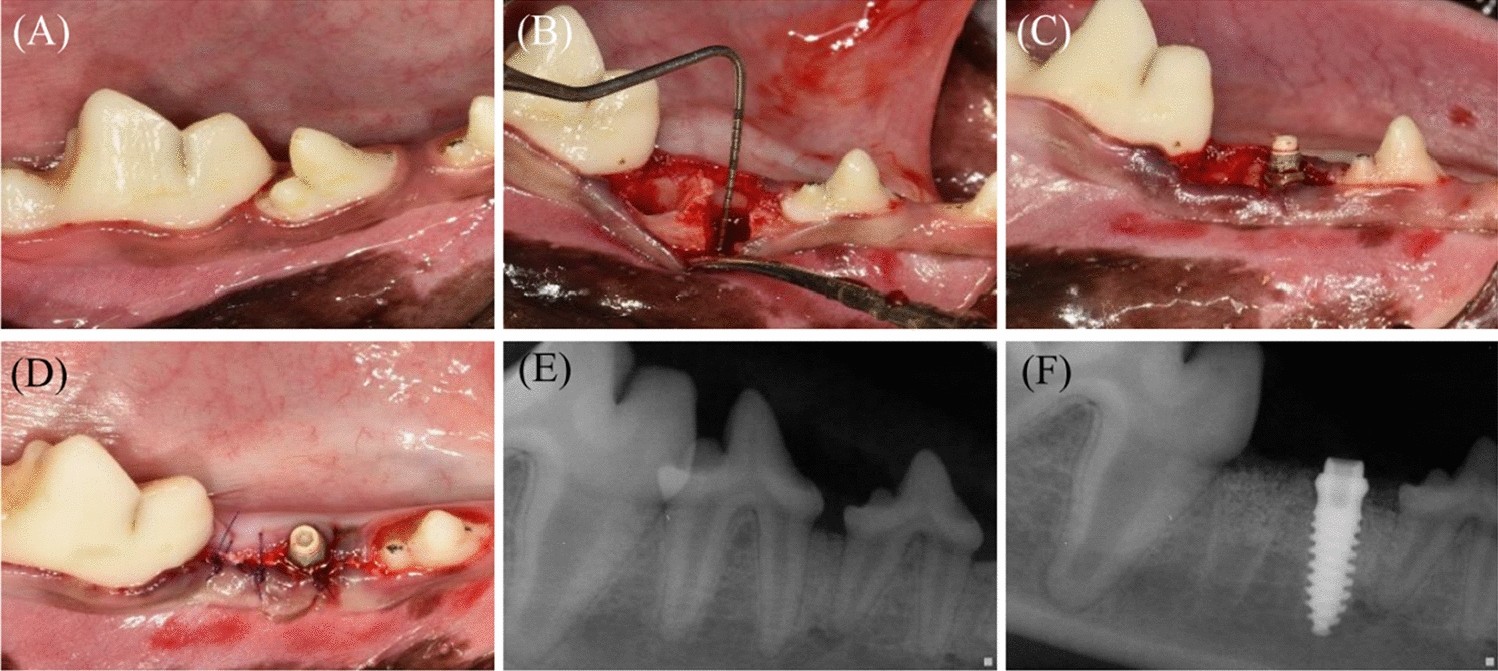

Figure 2

Clinical photographs and periapical radiographs. (A) Clinical photograph before the surgical procedure (B–D) Clinical photograph during surgery. After tooth extraction (bi-mandibular P4), 5-mm-high defects were created, and implants were placed with a simultaneous bone graft. (E) Periapical radiograph before surgery. (F) Periapical radiograph after surgery.